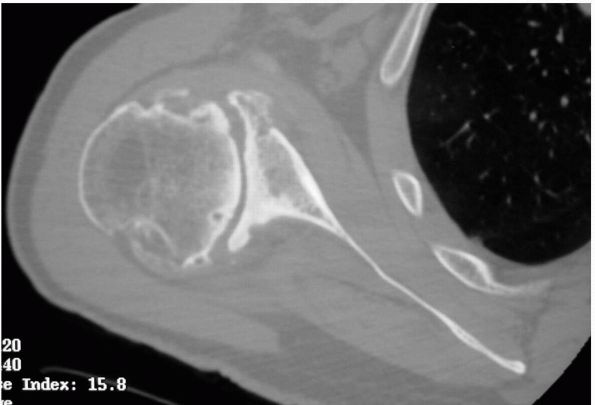

indications for each intervention.

![]() |

FIGURE 12-8. Axial CT image of the glenohumeral joint demonstrating posterior glenoid wear and subchondral sclerosis and cyst formation.